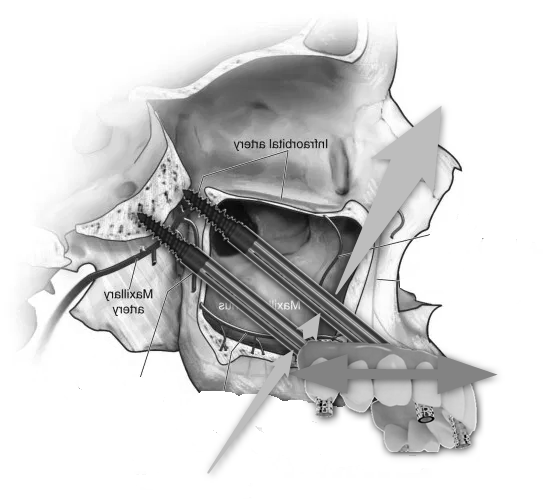

- Sinus Lift (Maxillary Sinus Elevation):

- At our center, we avoid this procedure thanks to Galileus Cerclage Sinus® surgery. In cases where the bone in the upper jaw is insufficient, a sinus lift procedure can be performed. This involves lifting the sinus membrane and adding bone graft material beneath it to improve bone density in the posterior maxilla.

- Zygomatic Implants:

- At our center, we avoid this procedure thanks to Galileus Cerclage Sinus® surgery. If not possible, we also avoid it with the Pterygoid Zygomatic technique. Zygomatic implants are longer implants anchored to the zygomatic bone (cheekbone). They are used when the maxillary bone is severely atrophied, providing an alternative to bone grafts or sinus lift procedures.